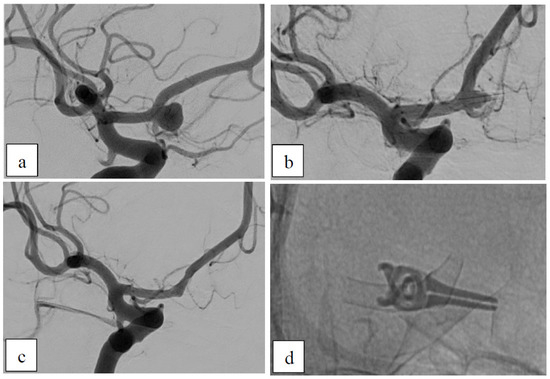

Case 1: Dysplastic Aneurysms

| 1 | 50 | f | P1/2 (two aneurysms) | bilateral | dysplastic | no | no | ASA+ Clopidogrel | left: B2 right: B2 | left: 3 | left: D1 right: − |